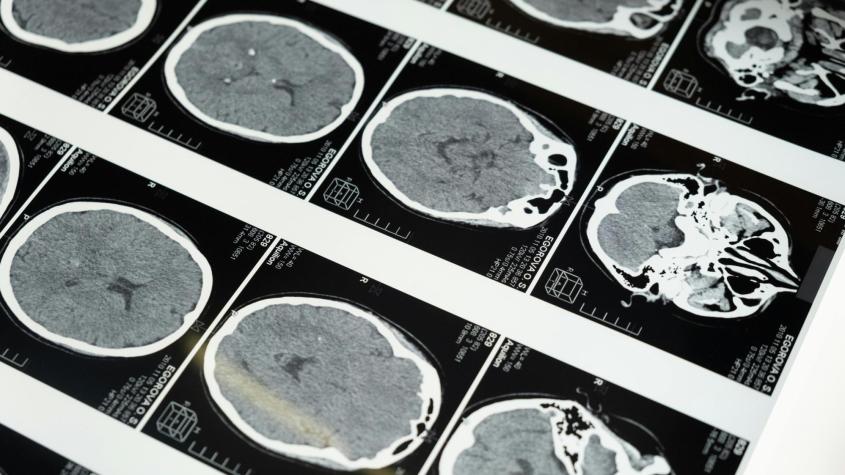

trombólisis